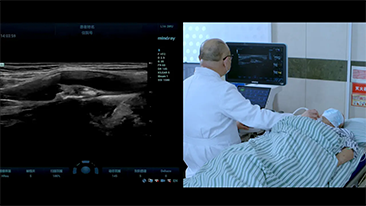

Bir karaci?er ne kadar net g?rĂŒlebilir?

Hemanjiyom veya karaci?er kanseri gibi fokal karaci?er lezyonlar? i?in, ultrason kontrast g?rĂŒntĂŒlemesi ?nemli bir rol oynar. Ultra geni? lineer olmayan UWN+ kontrast g?rĂŒntĂŒleme teknolojisi, daha dĂŒ?ĂŒk MI ve daha uzun perfĂŒzyon sĂŒresi g?zlemi ile daha iyi penetrasyon, daha yĂŒksek kontrast doku oran? elde edilmesine yard?mc? olabilir.